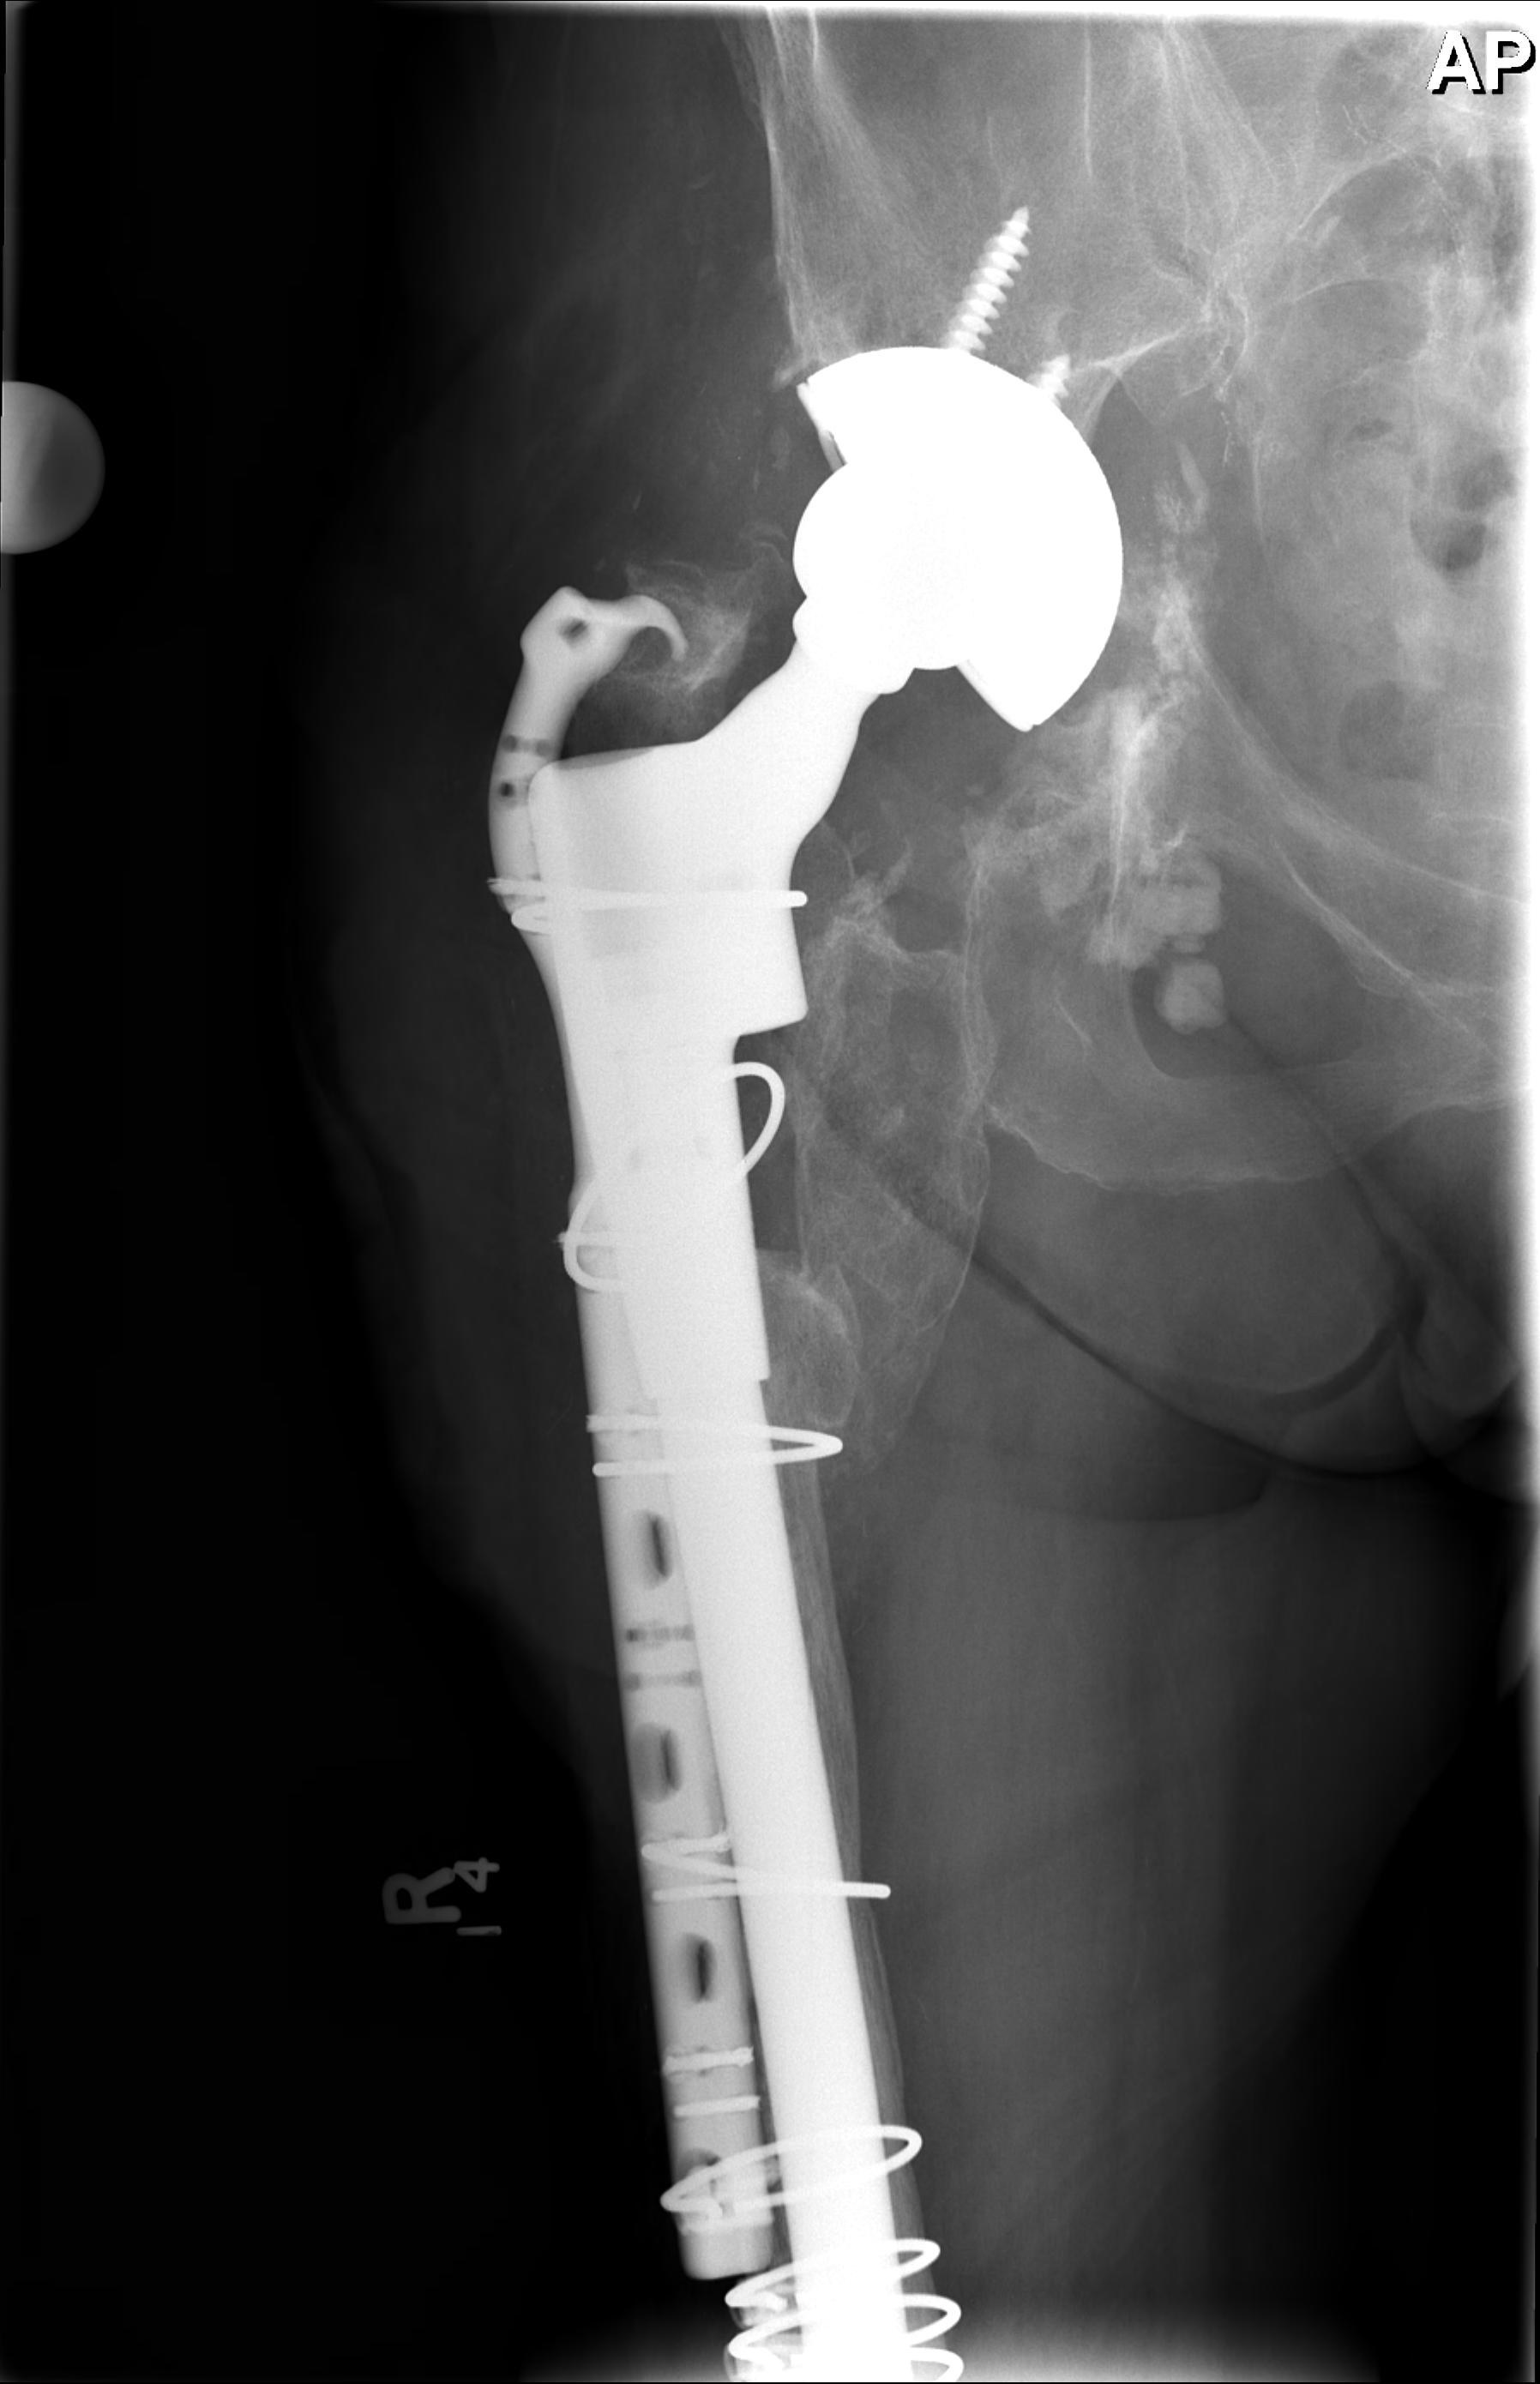

1. Long stem cemented revision femoral stem

2. Extensively porous coated diaphyseal fitting uncemented stem

D. Bulk Structural Proximal Femoral Allograft

Technique

- desired stem cemented into allograft

- press fit distally into host femur

- step cut graft host junction

- secure cerclage wire and onlay cortical strut

- proximal host bone wrapped around allograft with ABD preservation

- very important – abductor mechanism must be secured and protected